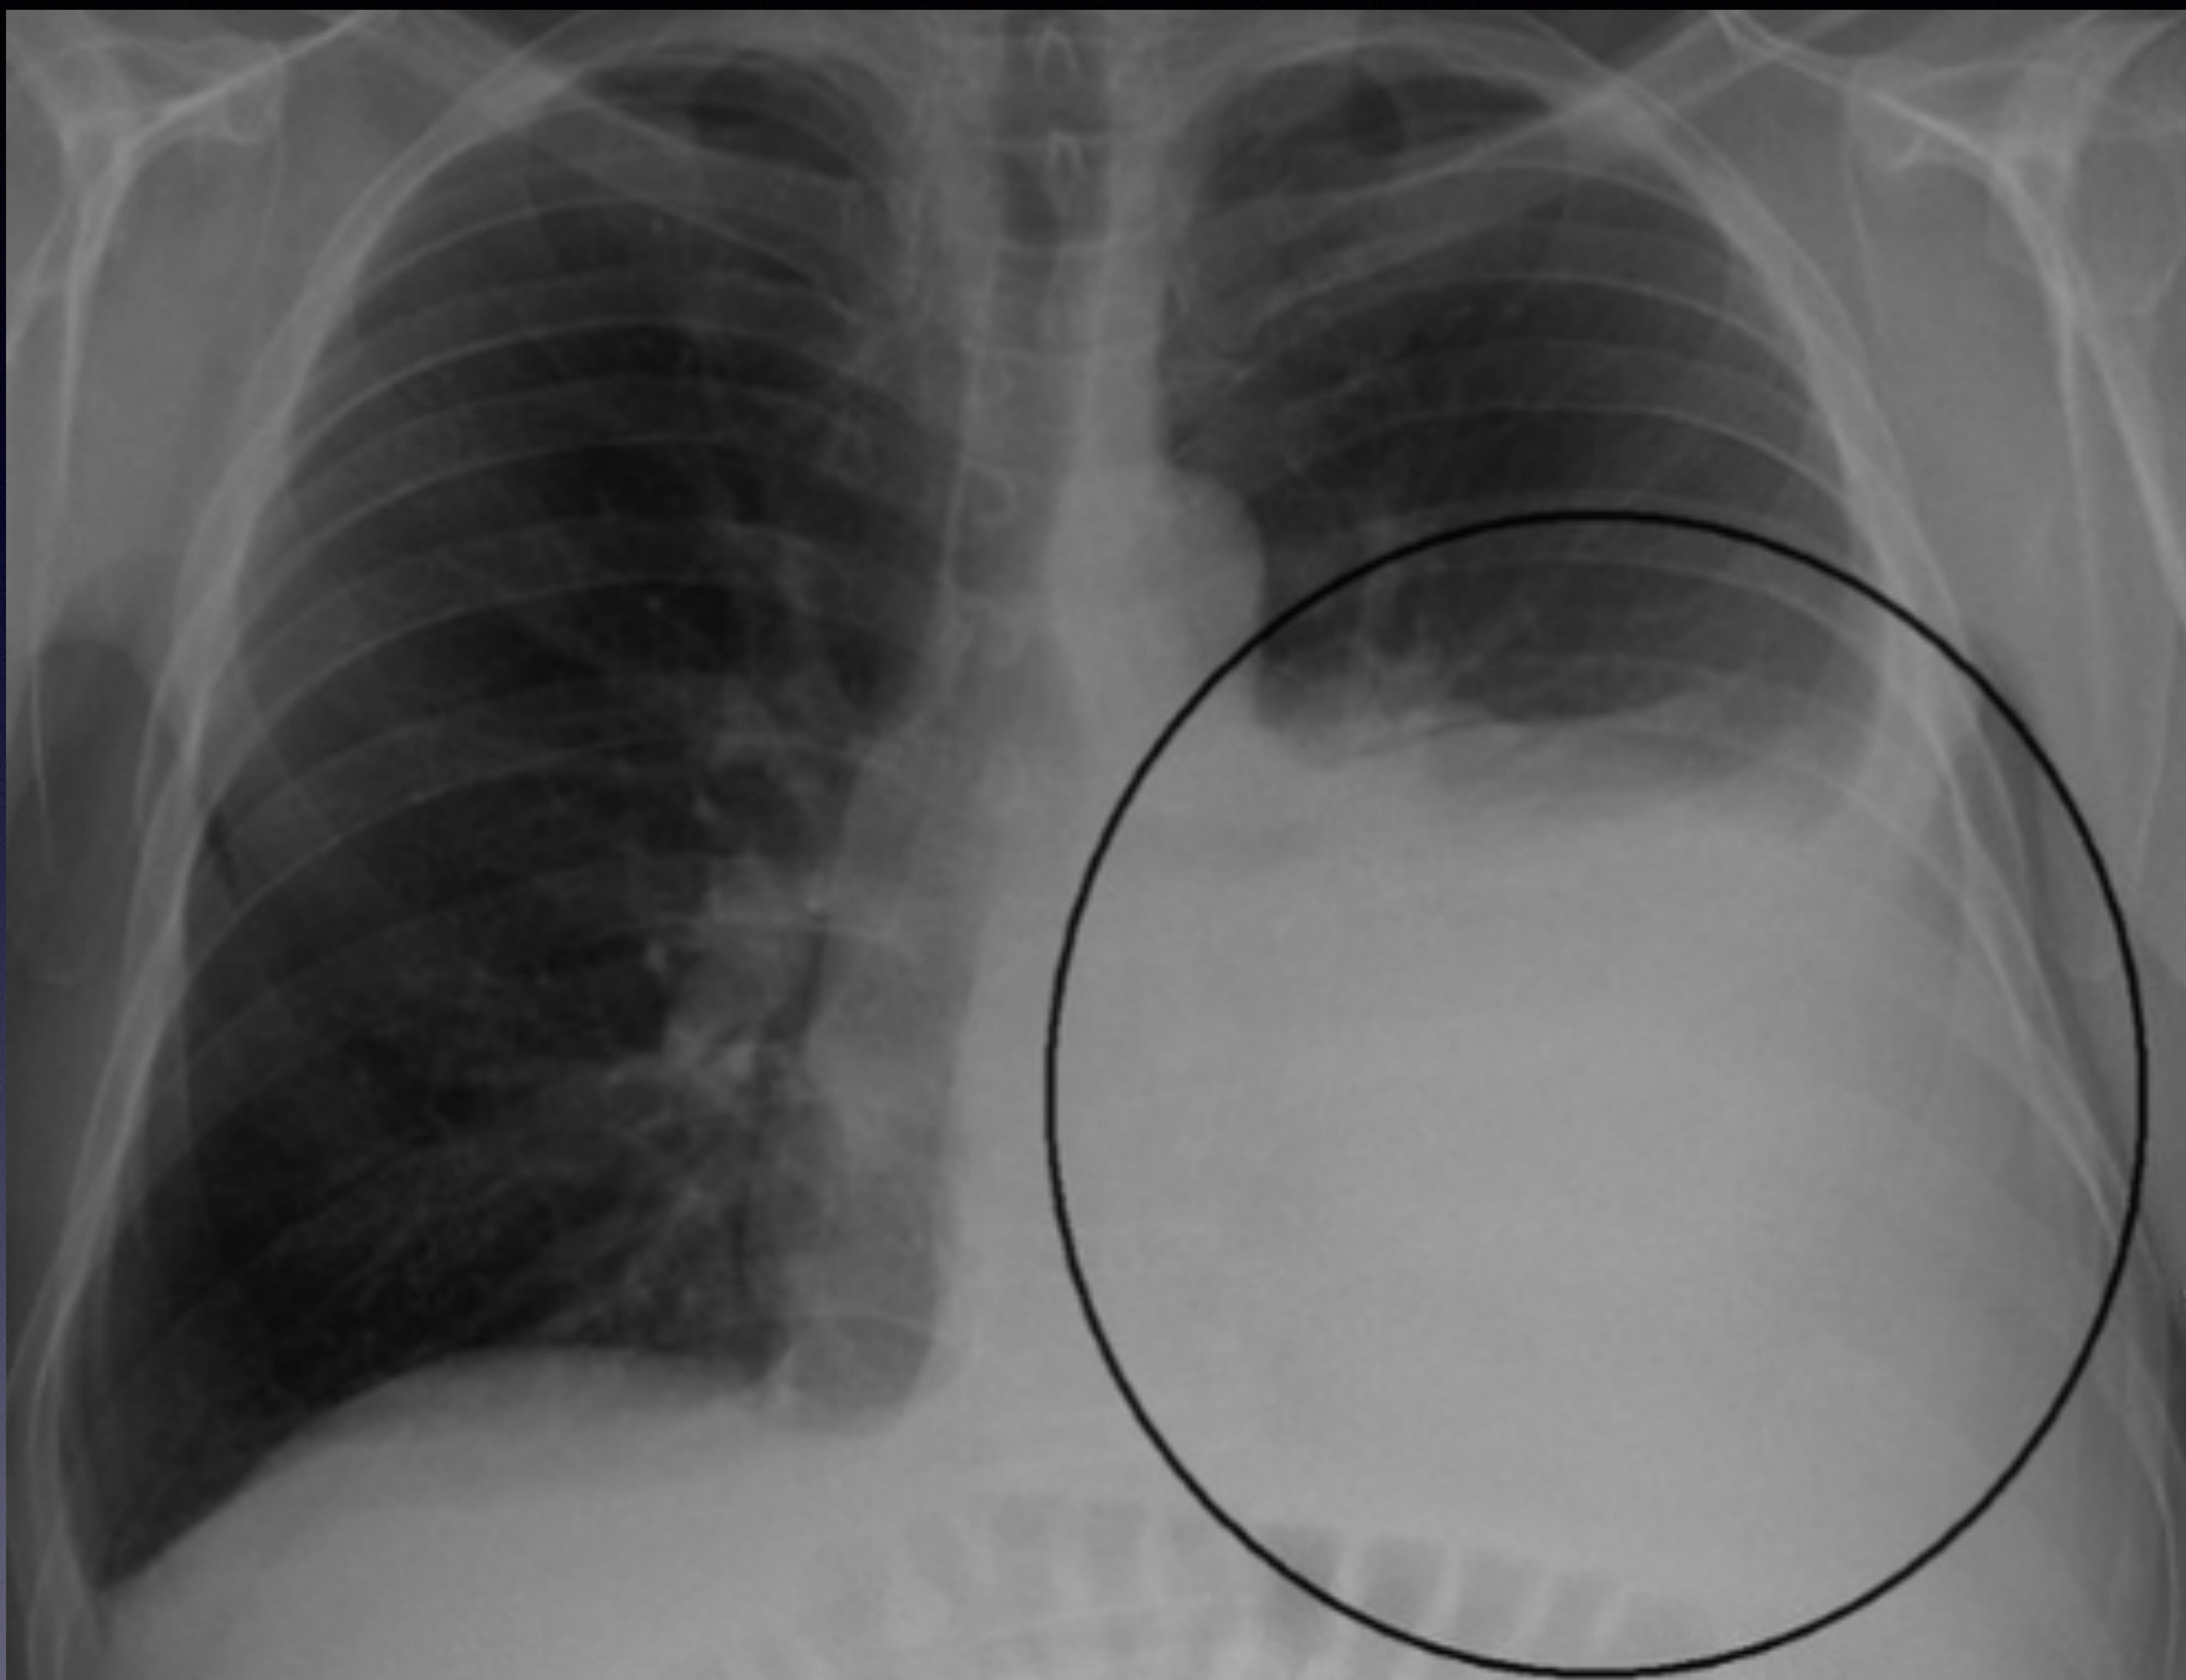

Chest X-ray consistent with Pleural Effusion (PE) or Hemothorax.

Massive Hemothorax

- Note: Do not rely on color. On Chest X-ray: > 2/3 of the available space in the hemithorax.

chest X-ray